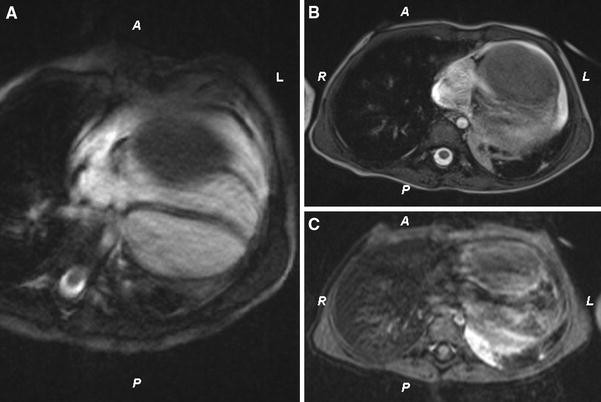

In a 6-month-old girl, a large cardiac tumor in the RV was discovered during evaluation for a soft systolic murmur. Except for the soft systolic heart murmur, the overall pediatric examination was normal. Echocardiography showed a large (4.0 × 4.5 × 4.0 cm) homogeneous mass appended to the RV free wall (Fig. 1). There was neither significant RV outflow tract obstruction nor stenosis of the tricuspid valve. Cardiac computed tomography (CT) and magnetic resonance imaging (MRI) confirmed the presence of a large intraventricular solid mass developed at the expense of the RV lateral wall (Fig. 2). Short-term follow-up assessment was complicated by an episode of symptomatic ventricular tachycardia, which was successfully treated with electric cardioversion and amiodarone. Oral therapy with amiodarone was continued under close echocardiographic and rhythmic monitoring with uneventful follow-up evaluation for 2 years.

Fig. 2

The presence of a solid tumor confirmed by magnetic resonance imaging